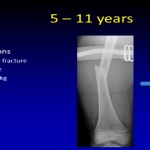

Growth Plate Injuries